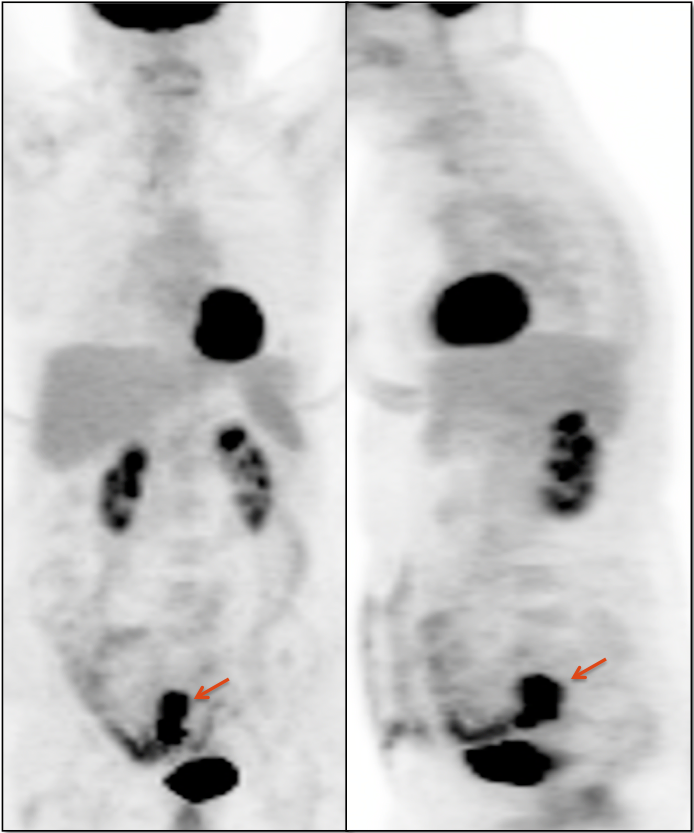

• Beware the small rectal cancer!  As the ano-rectal region frequently demonstrates intense physiologic uptake, it is very easy to overlook a rectal malignancy, especially if it is an incidental finding.  To avoid this error, always evaluate the rectum carefully on the sagittal whole body images.  It is shocking to see how readily apparent a rectal cancer can be on these images, yet so easily overlooked in the axial plane.